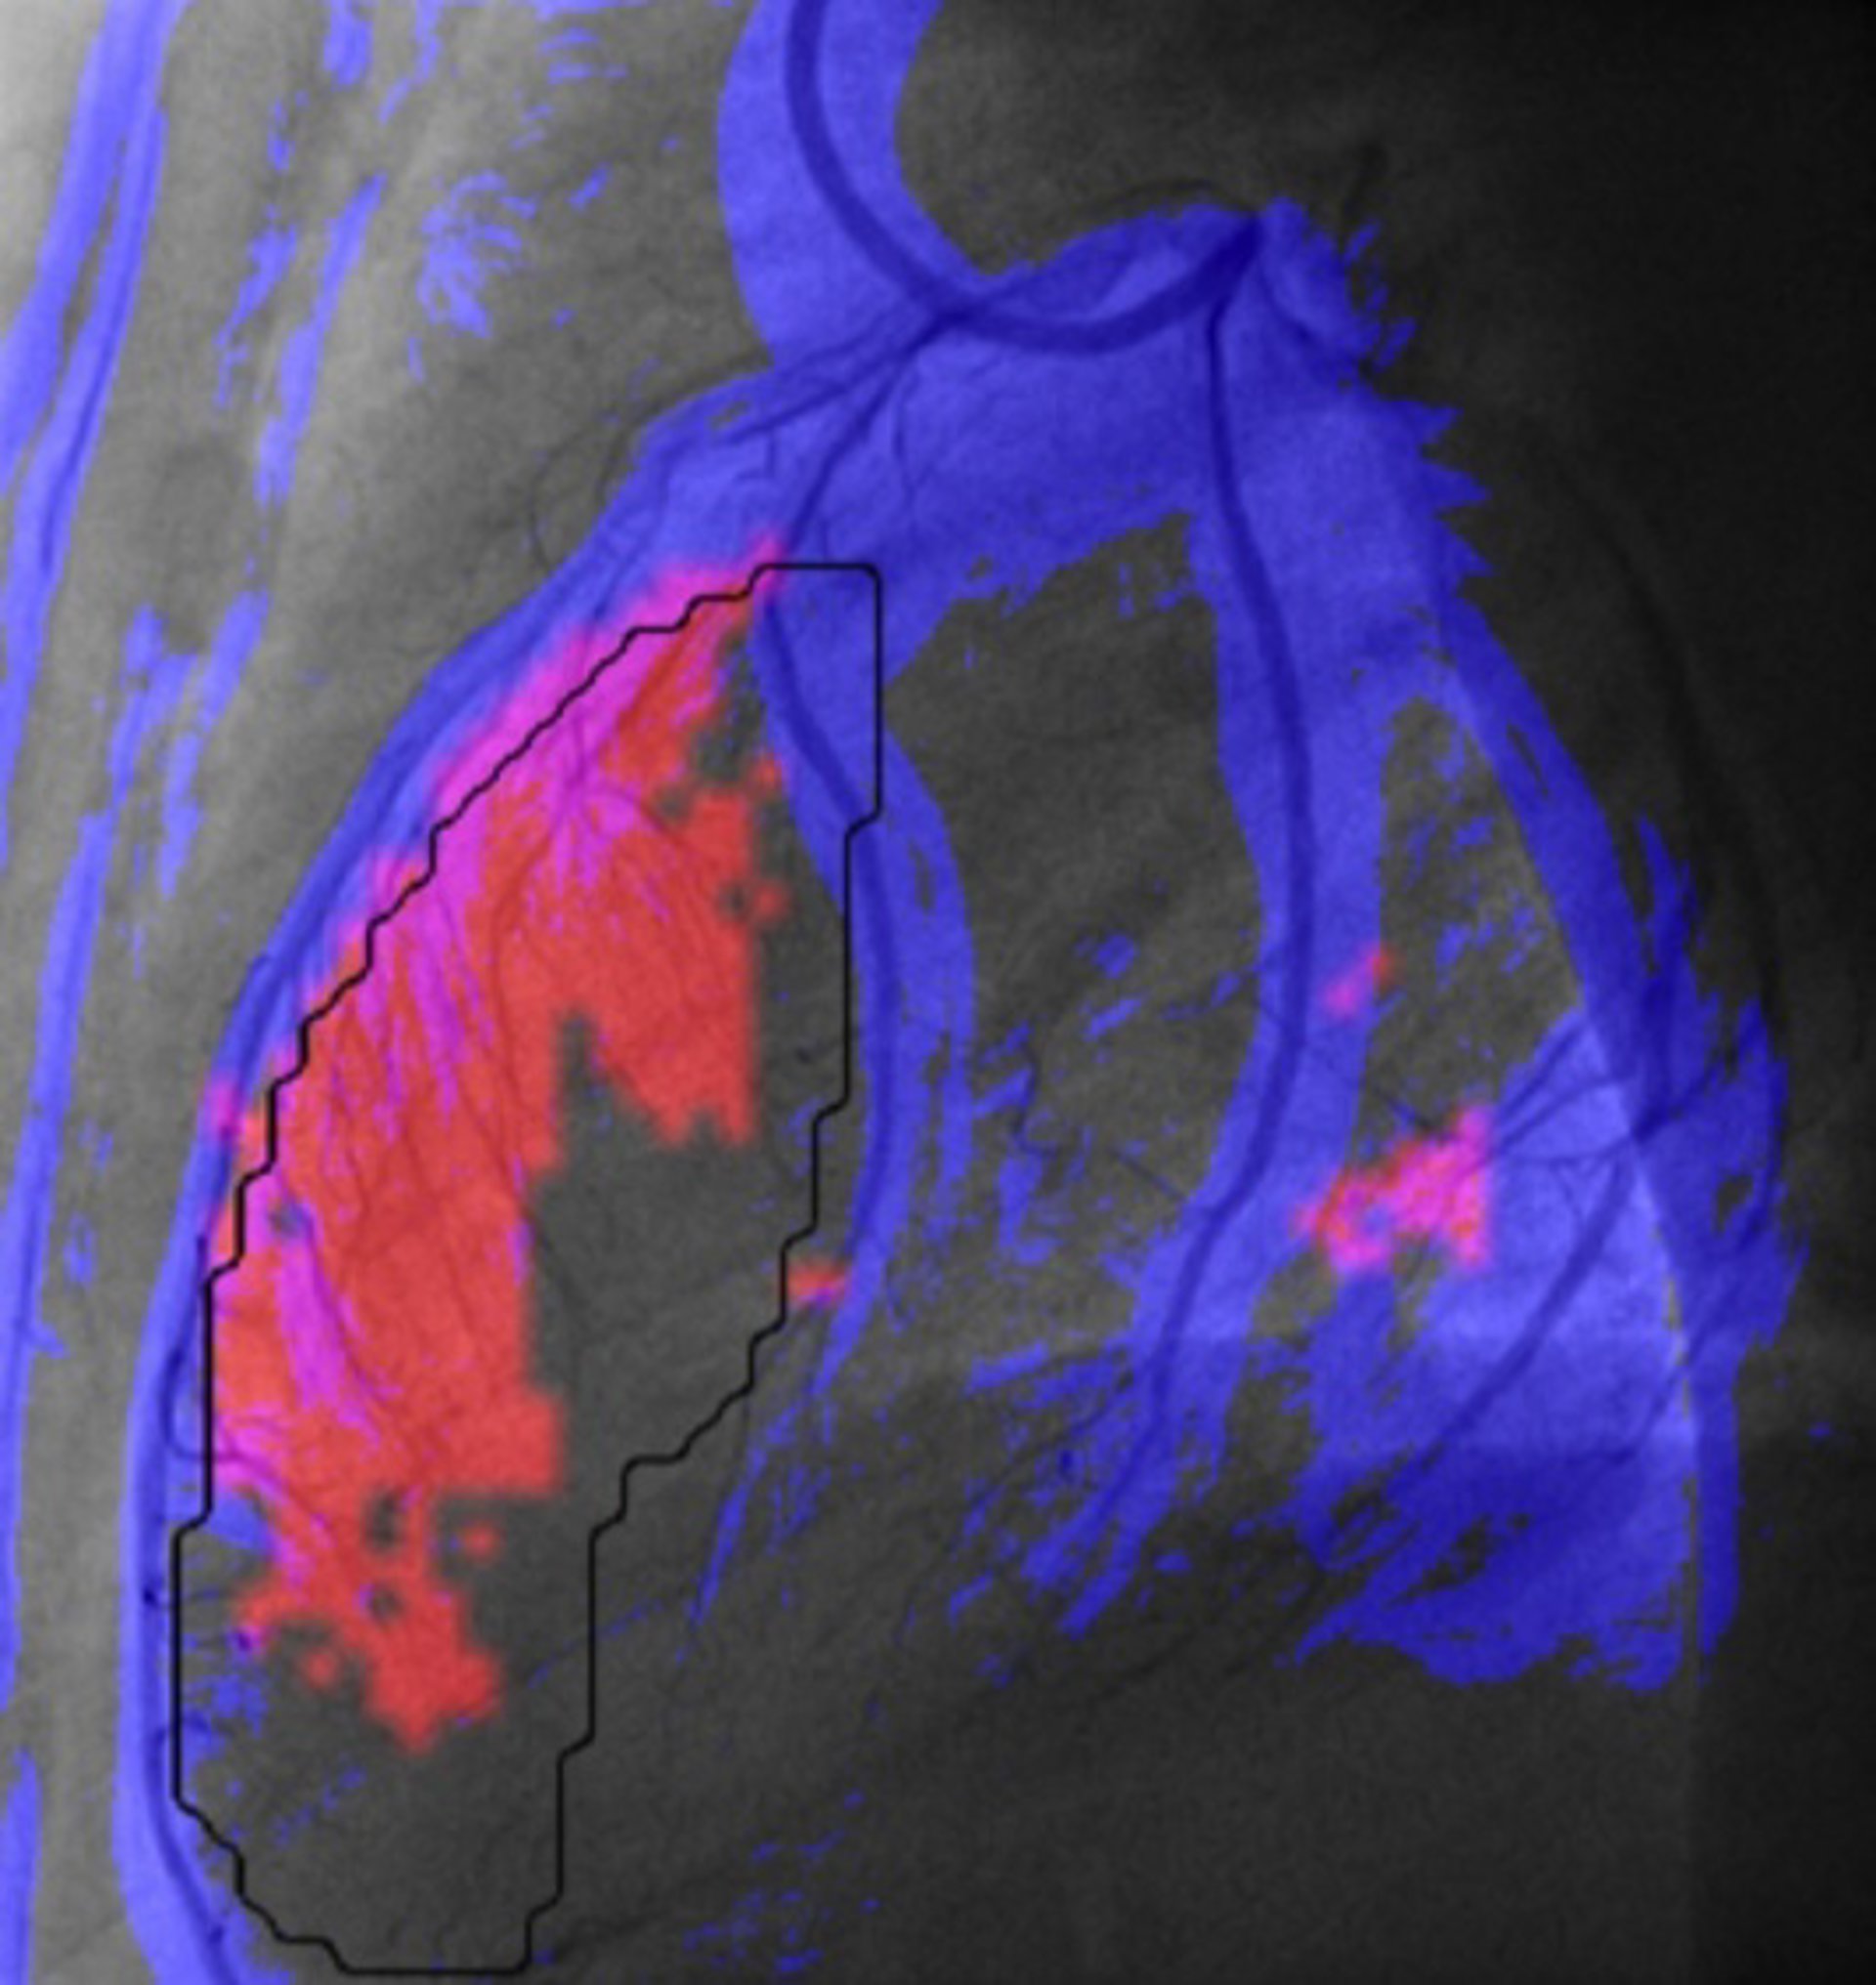

Investigadores del Centro de Visión para Computador (CVC) de la Universitat Autònoma de Barcelona (UAB) han diseñado una herramienta informática para mejorar y agilizar el diagnóstico de daño cardíaco después de sufrir un infarto.

A través del análisis de imágenes, la herramienta permite obtener una medida "cuantitativa, reproducible y más objetiva" de la irrigación miocárdica; identifica las regiones con menor riego sanguíneo, y facilita la comparación rápida entre los estados de antes y después de la operación, y entre dos arterias.